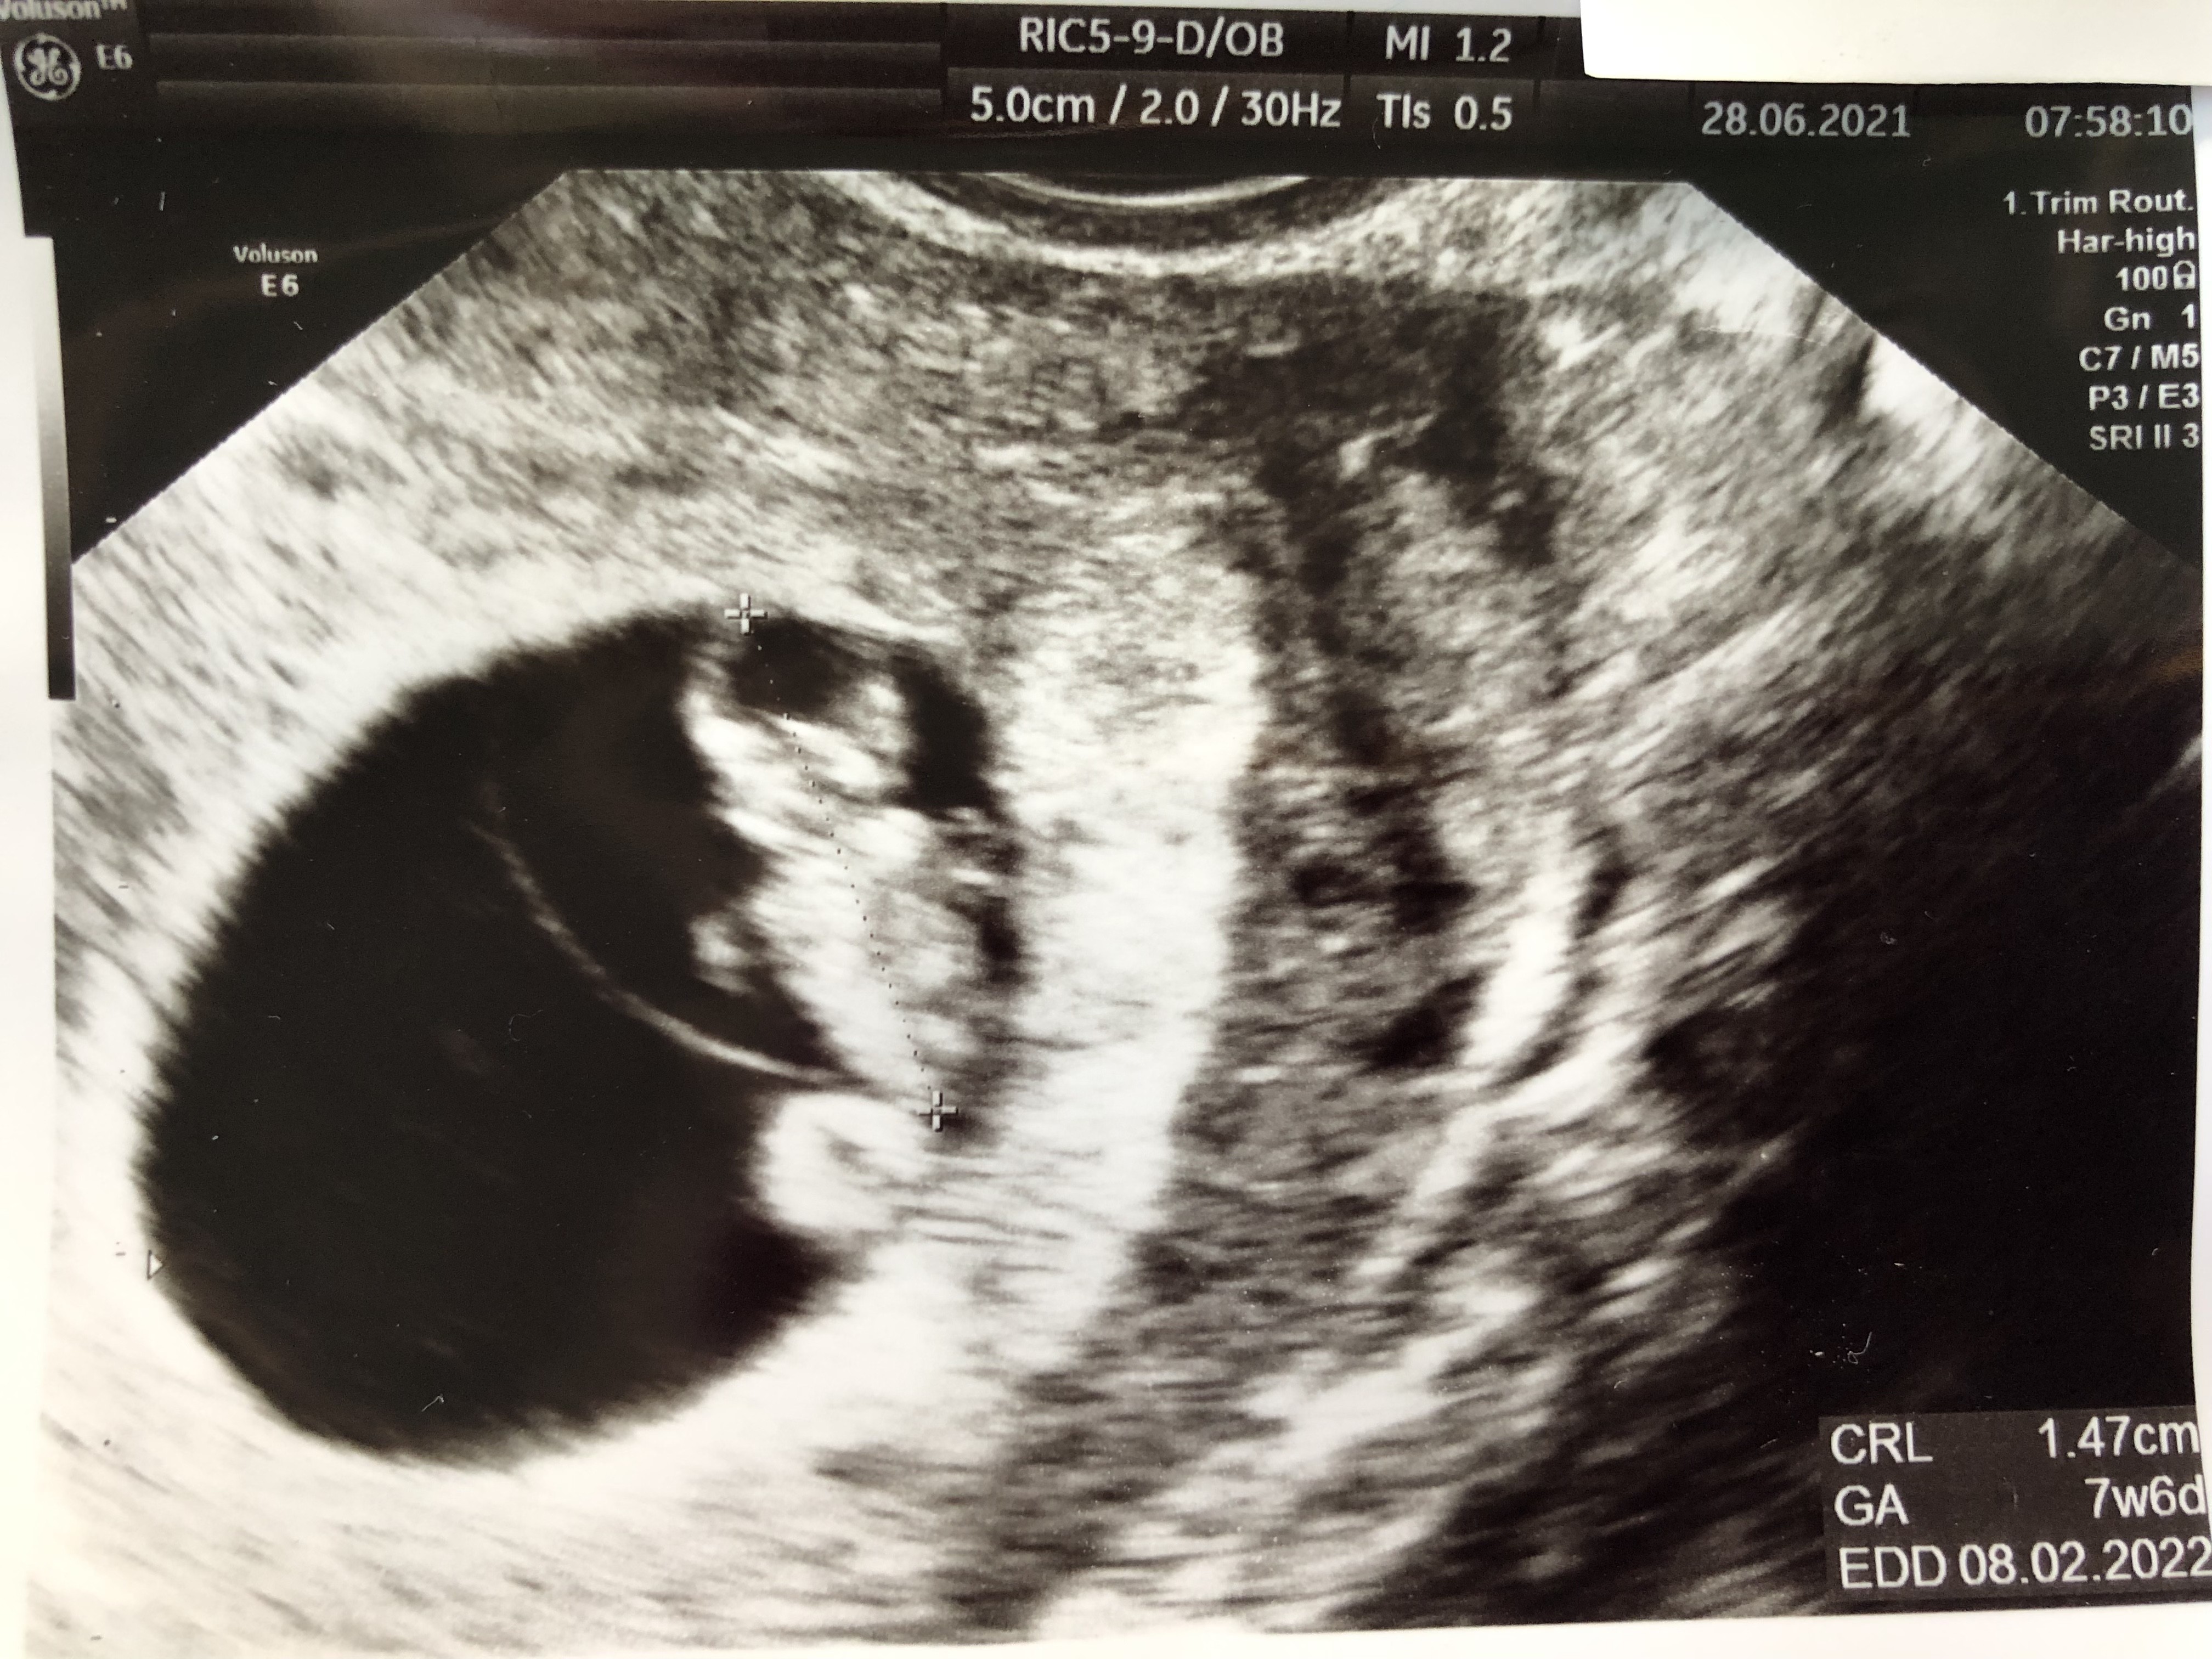

Lubię oglądać swoje (prawie codziennie 😁) i Wasze zdj. Usg. Bardzo ładne już dzieciaczki widać 😊 Ja na bieżąco wstawiałam, 4tyg temu kropeczkę i 2 tyg. temu fasolkę (lub oby dwa jednocześnie, nie pamiętam. Ale w piątek byłam na nieplanowanej wizycie u innego gin. i miał tak bardzo stare usg, i prawie nic nie było widać. No i brak łazienki w gabinecie, rozbierałam się przy nim 🤦‍♀️ Wstawię Wam dla porównania z 2 tyg temu i piątek. Teraz się nie dziwię, że niektórzy szybciej zobaczyli zarodek a inni czekali. I że na niektórych zdj widać już małego człowieczka, a u innych w podobnym tyg nie wiadomo co (tutaj mówię o swoim zdj i ogólnie obrazie usg) Już się nie mogę doczekać wizyty w pon żeby zobaczyć dokładniej rączki i nóżki no i ogólnie całokształt. Jestem w szoku, że prywatnie można spotkać tak stare sprzęty. Na NFZ wcale by mnie to nie zaskoczyło, ale w jednym i w drugim gabinecie płaciłam 200zł…

Załączniki

• 9FB9D23E-AAE0-49AE-8BC0-FA27ACA9CBCE.jpeg

9FB9D23E-AAE0-49AE-8BC0-FA27ACA9CBCE.jpeg

1,9 MB · Wyświetleń: 91